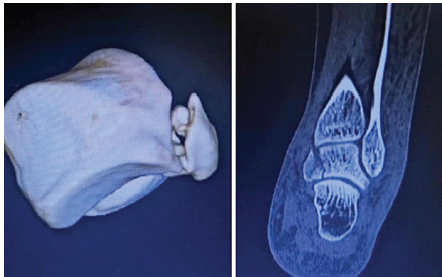

A 35-year-old male resident doctor presented with pain and swelling over the left ankle after slipping and falling on stairs. Examination revealed localized tenderness over the posteromedial aspect of the ankle with restricted movement. Plain radiographs (Fig. 1) appeared normal; however, due to high suspicion, a CT scan (Fig. 2) was performed, revealing a displaced fracture of the posteromedial process of the talus.

Figure 2: Pre-operative computed tomography showing displaced posteromedial process fracture (Cedell’s fracture).